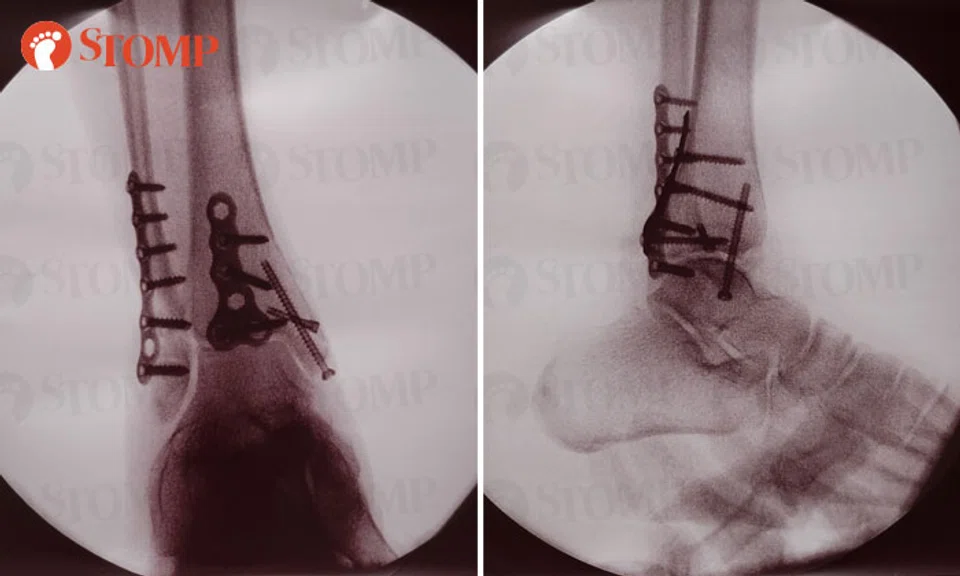

The Stomper had to undergo surgery following the injury. She shared X-ray images showing several screws implanted in her ankle.